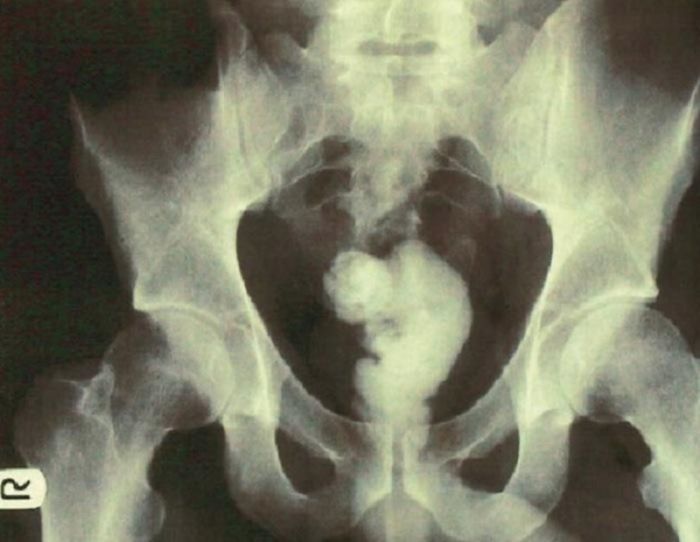

При ректальном исследовании твердое как камень инородное тело прощупывалось непосредственно внутри анального сфинктера. Обычный рентгеновский снимок брюшной полости показал инородный предмет, повторяющий контур прямой кишки, простирающийся от анального канала до ректосигмовидного соединения.

Не было явного расширения петель кишечника и признаков свободного газа в брюшной полости.